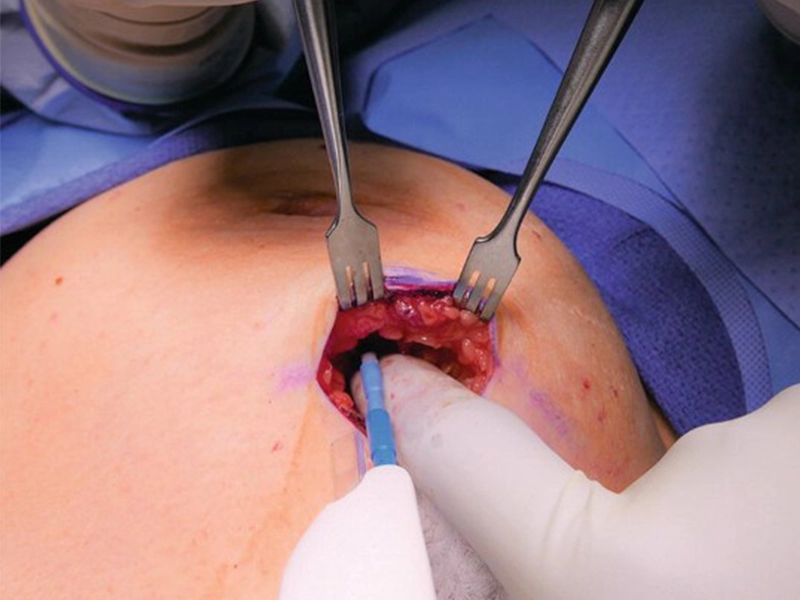

لامپکتومی یکی از پیشرفتهترین روشهای جراحی سرطان پستان است که امکان حذف توده سرطانی را با حفظ ظاهر طبیعی پستان

جراحی سرطان سینه یکی از اساسیترین و موثرترین راهکارها برای کنترل و درمان این بیماری به شمار میرود. این جراحی